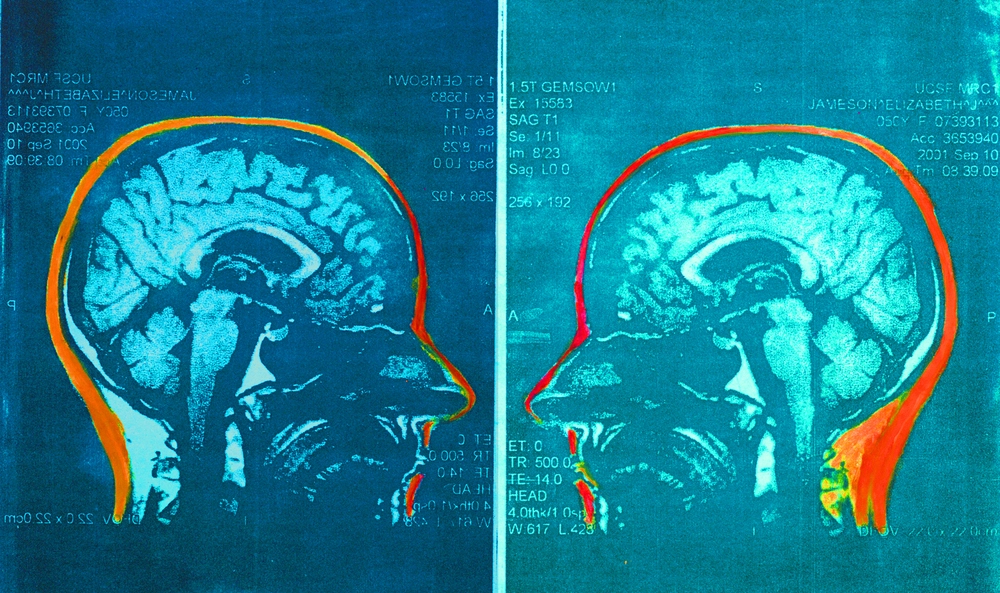

For several years now, Elizabeth has been using her disability as a form of communication, in which she transforms her MRI brain scans into incredible works of art — seeking to challenge how society views illness and disability.

In a small studio garage, Elizabeth began transforming her medical scans by etching them onto copper plates. Then, with the power of the printing press, she would add color to the sterile, black and white images — giving the brain scans new meaning. Now, Elizabeth also integrates mixed media and textile art practices into her work and continually seeks to evolve her craft.